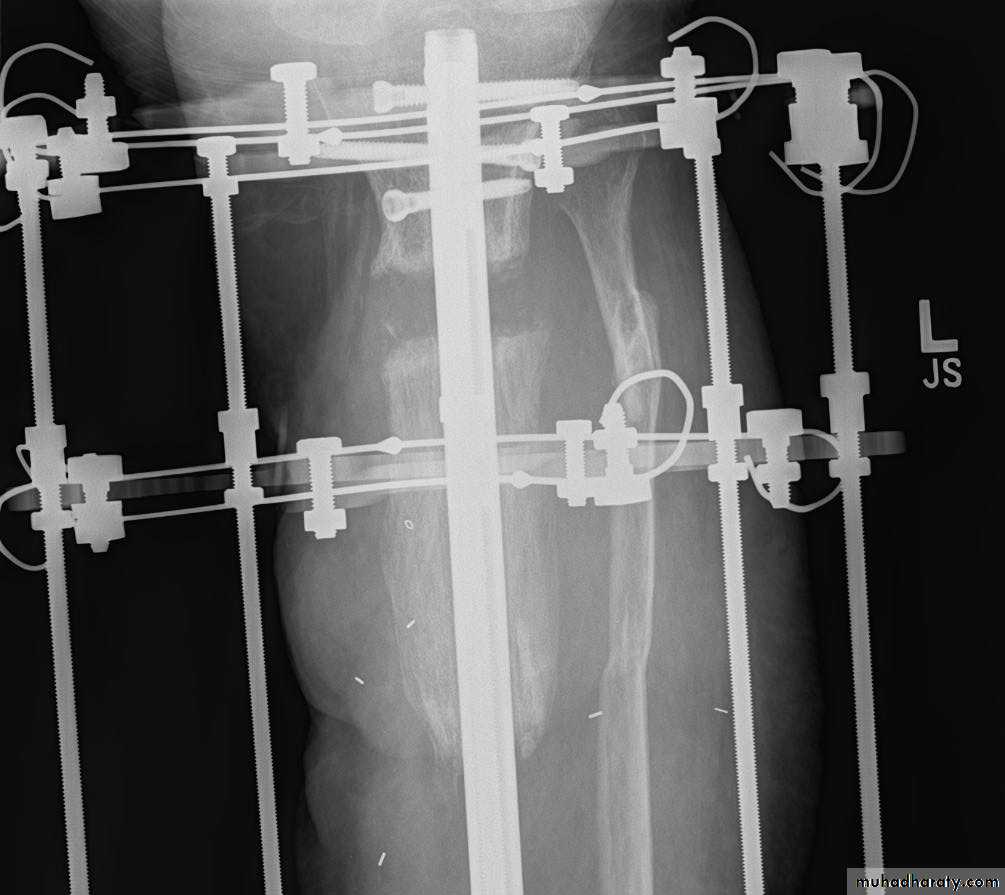

• Treatment: The wound should be left open for inspection and frequent dressing, and then delayed primary closure after few days. The fracture is fixed by external fixator.

• Appropriate antibiotic should be given from the beginning